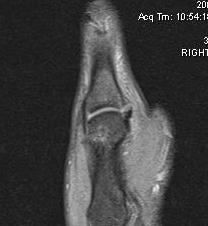

MRI

Look for stenar lesion

- when distal end of UCL

- flipped superficially over adductor aponeurosis

- will not be able to heal

A. Undisplaced

![]()

B. Displaced UCL